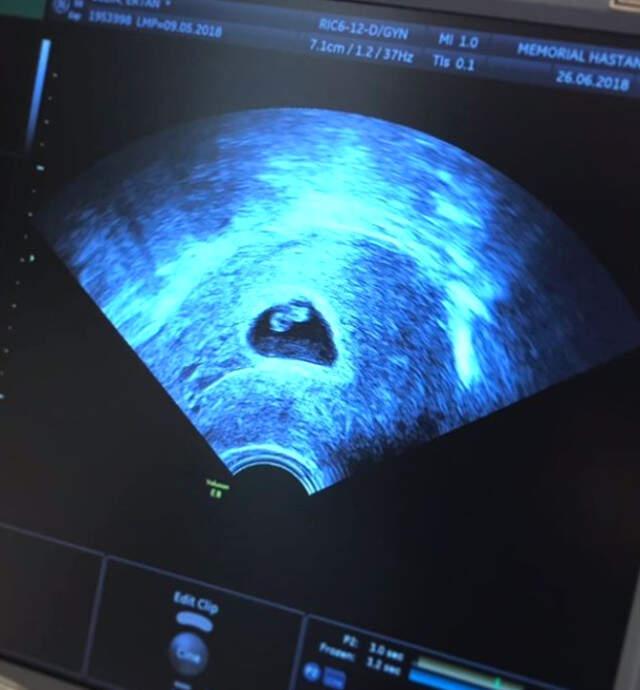

6 Haftalık Hamile Olan Siren Ertan, Bebeğinin Kalbinin Yavaş Attığını Öğrendi

6 haftalık hamile olan sosyetik güzel Siren Ertan, dün eşi ile gittiği kontrolde can sıkıcı bir durumla karşılaştı. Bebeğinin kalbinin yavaş attığını öğrenen Ertan takipçilerinden dua istedi.

‘HAYATA TUTUN NE OLUR’

Instagram hesabından ultrason fotoğrafı paylaşan Ertan, doğacak bebeği için şu mektubu yazdı: ‘Biz bugün doktorumuza gittik. Kalbinin sana kavuşmaya can atan benim kalbim kadar hızlı atamadığına çok üzgünüm bebeğim. Ben seni sımsıkı tutuyorum, sen de hayata tutun ne olur. Ben seni nasıl bir özlemle bekliyorum bir bilsen.